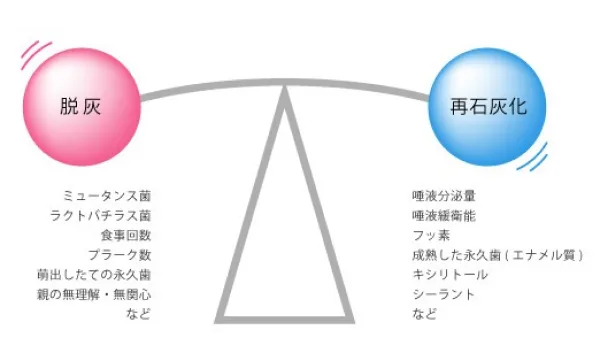

脱灰と再石灰化

健康な状態では、上図のように「脱灰(だっかい)」と「再石灰化」の力は拮抗していることになりますが、 「脱灰」に働く力が強くなったり、「再石灰化」に働く力が弱くなったときは脱灰が進んで歯が溶かされ、 虫歯が出来てしまいます。 ひとりひとりのお口の中でおきている「脱灰」と「再石灰化」のバランスを分析する事で、個人の虫歯のリスクを知ることが できます。そして、脱灰に傾いていると判定されたならば、それを様々な方法でコントロールし、再石灰化を促進したり 脱灰を抑制しなければなりません。

食事をとると、2~3分でプラーク中のpH(ペーハー)は酸性に傾き、脱灰がはじまります。この脱灰の時間が長く続いたり、酸性度が強いほど虫歯の危険が増加します。唾液の力によって 約20~40分間でプラーク中のpHが上昇し、再石灰化がはじまります。